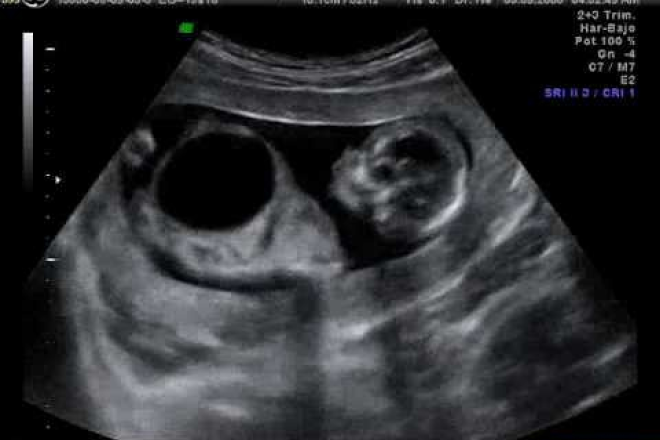

El propósito de esta investigación fue estudiar la correlación entre nódulos hipoecoicos detectados en la ecografía y la hiperplasia benigna de la glándula prostática de exterior diagnosticada por ecografía transrectal (USTR)-guiado biopsias. Métodos.- Las biopsias guiadas por USTR se realizaron en 472 pacientes con sospecha de tener cáncer de próstata.